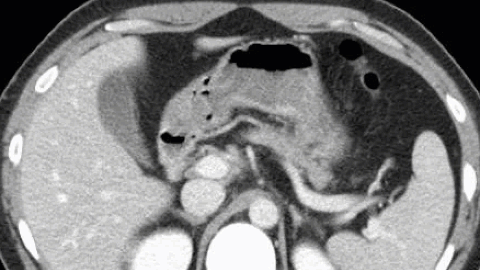

症例 50歳代女性

膵頭部の外側縁が凸状に前方に突出しています。

膵実質と類似した形状および濃度であり、こちらも膵頭部外側縁突出を疑う所見です。